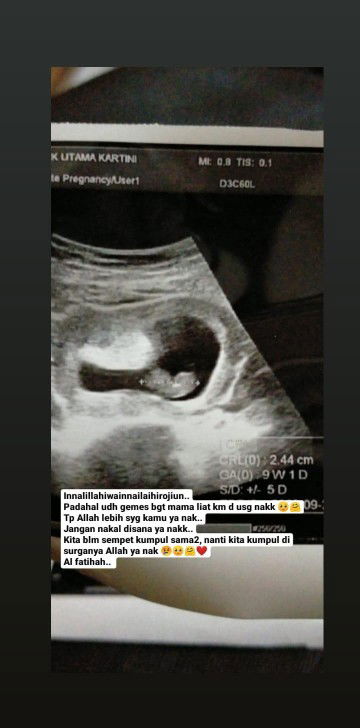

Janin 9 minggu meninggal dlm kandungan karena tidak berkembang

Sedih.. ga percaya.. Allah lebih syg sm janinku.. setelah drama 2 minggu lalu periksa di rs X yg bilang janinnya ga ada, sy cb periksa ke dokter lain. dan ternyata janin ada, bahagia nya aku melihat "utun" di layar. Tapi dokter tidak menemukan denyut jantung, dan ukuran yang harusnya 10 week, ternyata d usg saat itumasih 9 week. Dokter menyarankan untuk kembali lagi seminggu kemudian. Seminggu setelah kontrol, tepat hari senin 2 maret saya kontrol lagi. dan ternyatabenar saja, janinku tidakberkembang dan dinyatakan meninggal dlm kandungan.. hancurrr rasanya hati inii.. hari ini saya coba kembali ke rs X yg sebelumnya usg ga keliatan janin nya. hnya ingin memastikan lagi, dan saat usg, ya janin ada, tp dokter menyatakan hal yang sama. Janin tidak berkembang. saya ga mengeluarkan flek sedikitpun selama ini. dokter bertanya apakah pernah minum penguat kandungan? saya jwb ya, krna dl saat usia 5 week saya mengalami kram perut luar biasa setelah naik mtr kena lubang. ternyata itu adalah penanganan yang salah. krna penguat itu membuat kantung rahim menempel kuat di diding rahim meskipun janin sudah tidak berkembang. dan sangat berbahaya jika melakukan tindakan kuret ataupun pk obat peluruh . akhirnya saya di beri vitamin untuk badan saya agar sehat dan bisa membuat kantung rahim itu lepas dengar sendirinya. mohondoanya bunn.. agar semua bisa saya lewati dengan mudah dan diberikan ketabahan. ????